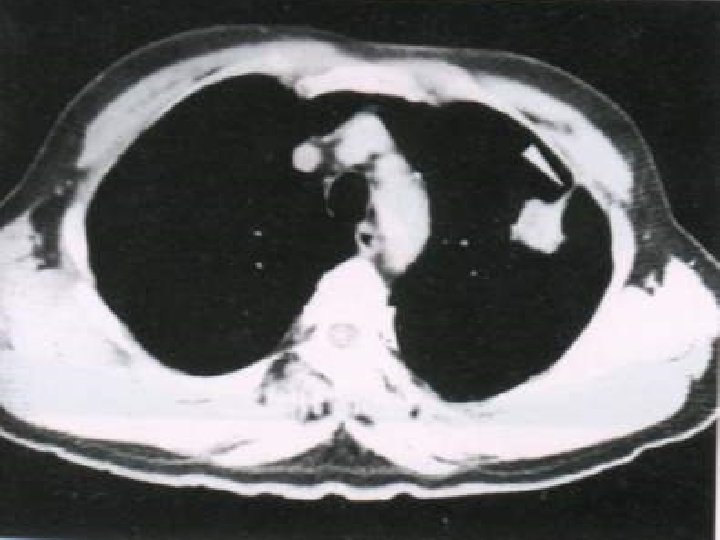

DIAGNOSIS 1. 2. 3. 4. 5. 6. 7. 8. 9. 10. x-ray examination. CT chest. MRI chest cytological examination of sputum. Bronchoscopic examination. Mediastinoscopy. Needle biopsy. Percutaneous transthoracic Lymph nodes biopsy. Supraclavicular, cervical, axillary. Pleural effusion examination. Thoracic exploration.